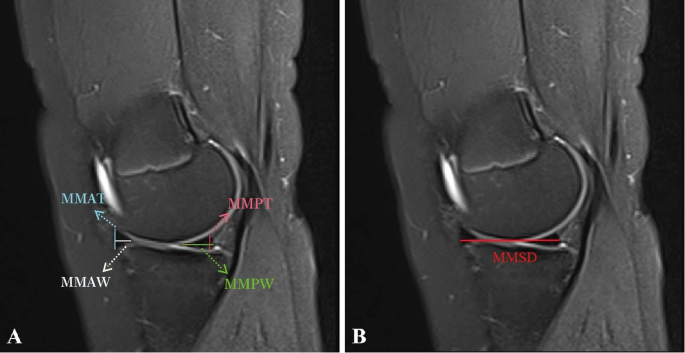

On the coronal images of the T2WI sequence, the measurements were as follows: the lateral meniscal body thickness (LMBT), the lateral meniscal body width (LMBW), the medial meniscal body thickness (MMBT), the medial meniscal body width (MMBW), the tibial plateau width (TPW), the lateral tibial plateau width (LTPW), the medial tibial plateau width (MTPW), the tibial intercondylar ridge width (TIRW), and the tibial intercondylar ridge height (TIRH) (Fig. 2). On the sagittal images of the T2WI sequence, the measurements were as follows: the lateral meniscal anterior horn thickness (LMAT), the lateral meniscal anterior horn width (LMAW), the lateral meniscal posterior horn thickness (LMPT), the lateral meniscal posterior horn width (LMPW), the lateral meniscal sagittal diameter (LMSD), the medial meniscal anterior horn thickness (MMAT), the medial meniscal anterior horn width (MMAW), the medial meniscal posterior horn thickness (MMPT), the medial meniscal posterior horn width (MMPW), and the medial meniscal sagittal diameter (MMSD) (Figs. 3 and 4). Although the study performed measurements on T2WI, the researchers reviewed T1WI and fat-suppressed sequences to confirm meniscal boundaries and to exclude abnormalities.

Measurements of the medial meniscus in sagittal position of MRI.